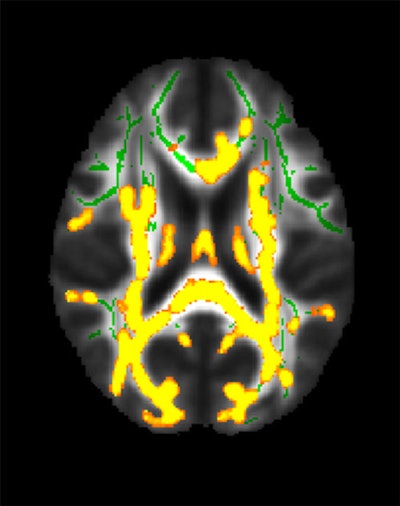

This figure shows increased neuroinflammation (yellow colors) associated with higher hidden fat (visceral fat) in the cohort of 54 participants with an average age of 50 years in the brain’s white matter. The green colors are the normal white matter. Image courtesy of the RSNA.

Dolatshahi and colleagues found that a higher ratio of visceral to subcutaneous fat was linked to higher amyloid PET tracer uptake in the precuneus cortex, a region affected by amyloid pathology in Alzheimer's disease – a result that was worse in men compared with women. The researchers also found that higher visceral fat measurements were linked to increased inflammation in the brain.

"Inflammatory secretions of visceral fat -- as opposed to potentially protective effects of subcutaneous fat -- may lead to inflammation in the brain, one of the main mechanisms contributing to Alzheimer's disease," Dolatshahi said.